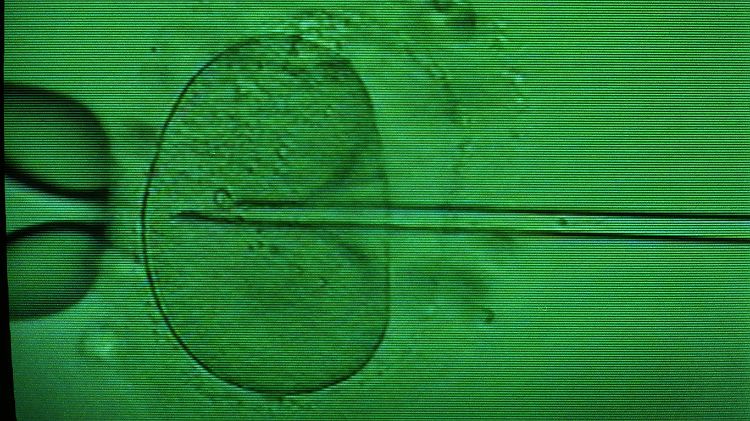

Einbringen einer Samenzelle in eine Eizelle mittels Mikropipette unter dem Mikroskop beim sogenannten "Retortenbaby-Verfahren" (In-vitro-Fertilisation).

(Foto: picture-alliance / dpa)